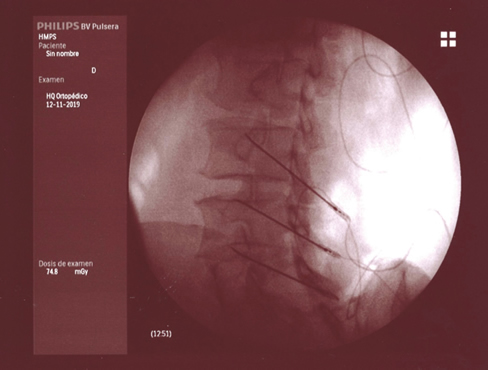

La neurotomía por radiofrecuencia del ramo medial es una técnica que está bien estandarizada a nivel cervical y lumbar, no así a nivel torácico, y que es un tratamiento que está bien establecido y estudiado con un nivel de evidencia alto (2,3,4). Por tanto, tras llegar al diagnóstico de dolor facetario el tratamiento de elección es la neurotomía por radiofrecuencia del ramo medial (Figuras 1 y 2).

Fig. 1.

Fig. 2.

La neurotomía por radiofrecuencia del ramo medial es una técnica estandarizada a nivel cervical y lumbar, con unos niveles de evidencia elevados y, por tanto, totalmente recomendable en el tratamiento del dolor facetario secundaria a la artrosis vertebral.